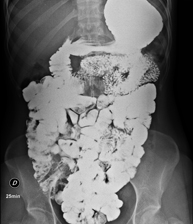

Prueba diagnóstica que consiste en obtener imágenes radiológicas en movimiento del esófago, el estómago y el duodeno mediante el empleo de rayos X (fluoroscopia) y de un contraste opaco baritado que se administra por vía oral. - Tránsito intestinal

Prueba diagnóstica que consiste en obtener imágenes radiológicas en movimiento del esófago, el estómago, el duodeno y el intestino delgado mediante el empleo de rayos X (fluoroscopia) y de un contraste opaco baritado que se administra por vía oral. - Enema opaco doble contraste

Prueba diagnóstica que consiste en obtener imágenes radiológicas del intestino grueso (colon y recto) mediante el empleo de rayos X. Se utiliza un contraste opaco que se administra a través del recto, en forma de enema y, también, se introduce aire para expandir el colon.